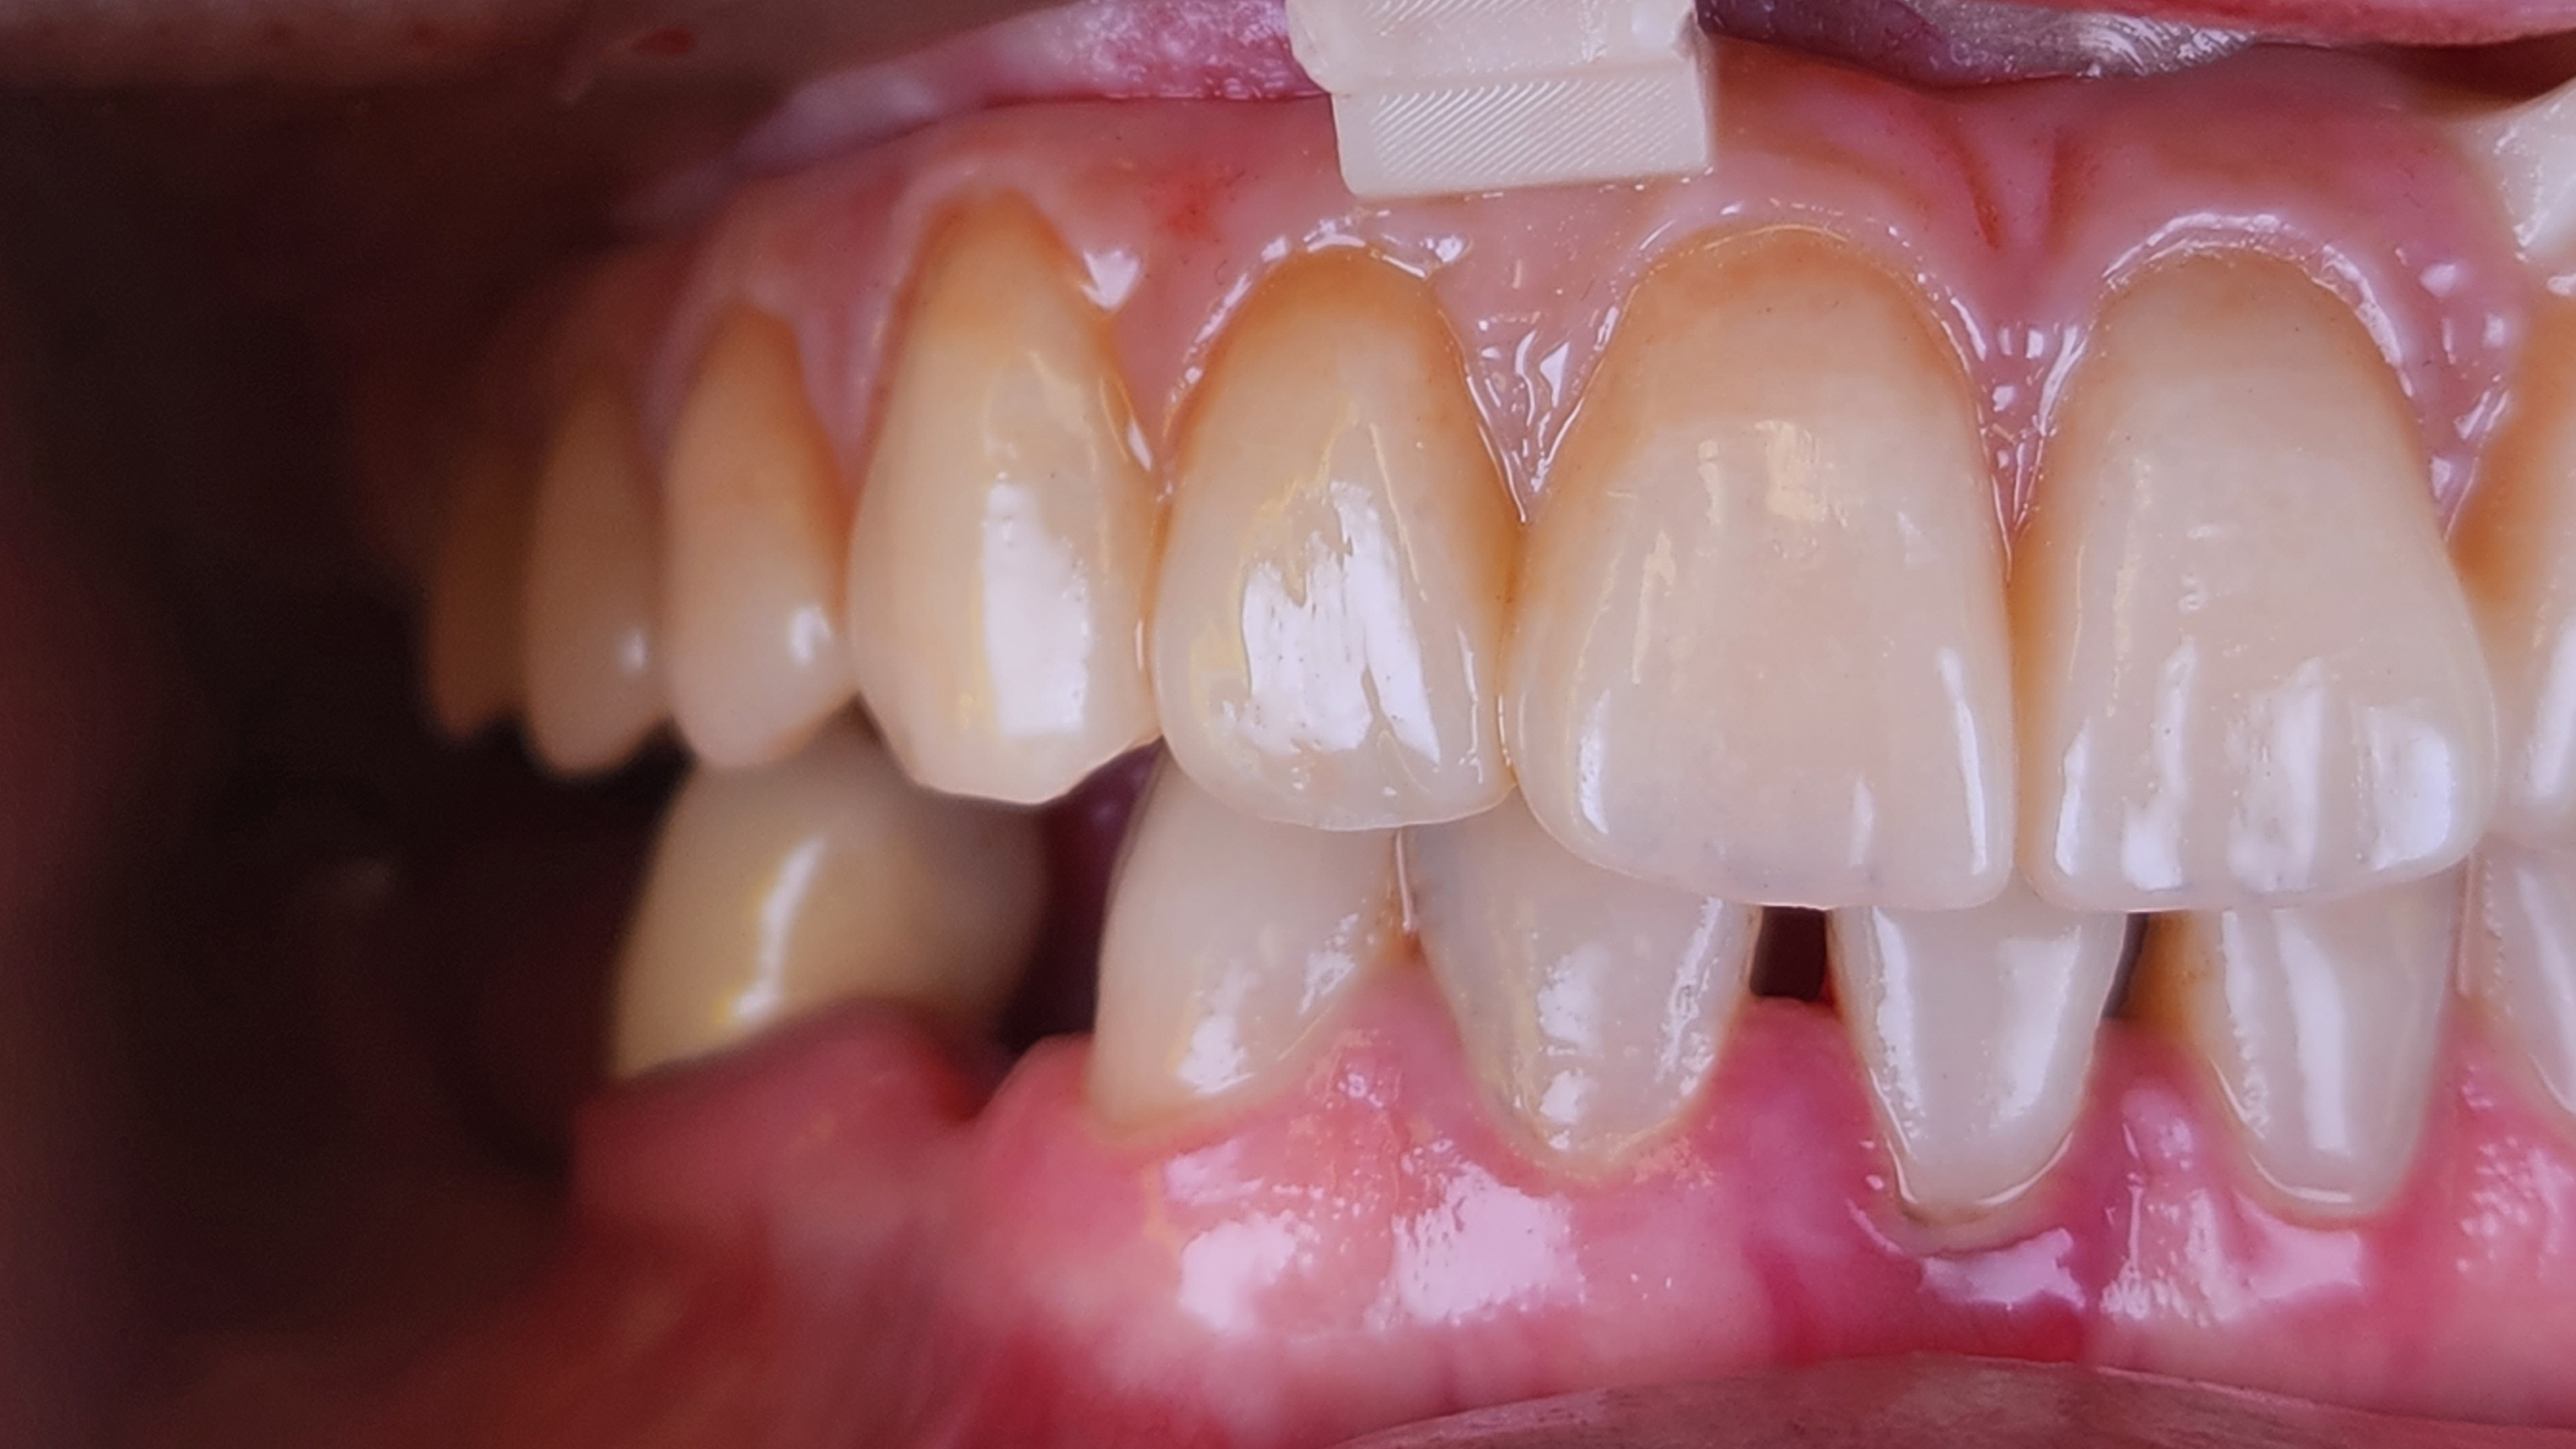

La componente protesica MultiUnit e TiBase per MultiUnit sono tutti rigorosamente IPD DentalGroup (IPD AbutmentCompatibili.com). I MUA MultiUnit con la loro ricopertura in TiN coating permette una perfetta stabilità tissutale e un mimetismo cromatico perfetto; il TiBase, anche esso ricoperto in TiN Coating, permette di mimetizzare il componente anche sotto a strutture stampate o con trasparenze e offre una grande sicurezza di adesione grazie alla sua geometria ottimizzata. Un aspetto cruciale di questo trattamento è stato l'uso della chirurgia guidata, che ha permesso un'accurata pianificazione e posizionamento degli impianti con una precisione senza precedenti. Il punto di forza di questa tecnica è l'introduzione delle dime scomponibili, o "stackable", che rappresentano una vera innovazione nel campo. Queste dime permettono di eseguire la chirurgia in fasi multiple, con la possibilità di aggiungere o rimuovere strati per accedere in modo controllato alle diverse fasi del procedimento. Questo sistema, non solo garantisce una maggiore precisione nell'installazione degli impianti, ma riduce anche il tempo chirurgico, minimizzando il disagio per il paziente e accelerando il recupero. L'impiego delle dime stackable dimostra come l'odontoiatria possa beneficiare in modo significativo dell'avanzamento tecnologico, migliorando l'efficienza e l'esito dei trattamenti. La decisione di utilizzare connessioni MUA Multi-Unit Non Engaging (IPD DentalGroup - Abutment Compatibili) è stata guidata dalla necessità di ottimizzare la flessibilità e la funzionalità del trattamento. Queste connessioni offrono una soluzione efficace per gestire la distribuzione delle forze masticatorie, particolarmente vantaggiosa in riabilitazioni complesse come quella realizzata con il Toronto Bridge. La scelta di abutment non engaging ha inoltre favorito una migliore gestione delle discrepanze angolari, facilitando il posizionamento degli impianti e l'adattabilità delle strutture protesiche (Fig .12, Fig. 13). Il trattamento ha portato a risultati eccellenti, migliorando significativamente la qualità di vita del paziente. La protesi tipo Toronto Bridge si è integrata armoniosamente, offrendo un aspetto naturale e duraturo (Fig. 14).

La decisione di utilizzare connessioni IPD MUA Multi Unit Non Engaging (IPD DentalGroup-Abutment Compatibili) ha arricchito ulteriormente il processo, offrendomi la flessibilità necessaria per adattare la protesi in modo che si integrasse perfettamente, non solo con l'aspetto fisico, ma anche con la vita del paziente. Questa scelta, benché tecnica, nasconde un profondo impegno verso il benessere del paziente, un principio che guida ogni nostra azione professionale (Fig. 3). Quando ho osservato la protesi completa per la prima volta, stampata con precisione e poi delicatamente ricoperta in composito, ho sentito un misto di orgoglio e umiltà. Questo non era solo il culmine di un trattamento odontoiatrico, ma la manifestazione fisica della mia passione e dedizione. Ogni dettaglio, dalla selezione dei materiali alla cura nella finitura, era un riflesso del mio viaggio personale nell'odontoiatria digitale (Fig. 4). Condividere questo risultato con il clinico e il paziente è stato un momento che ricorderò per sempre. Vedere la sua espressione trasformarsi, da timida speranza a gioia incontenibile, mi ha ricordato perché ho scelto questa carriera. L'odontoiatria digitale e la stampa 3D non sono solo avanzamenti tecnologici; sono strumenti che, nelle mani giuste, possono trasformare vite. Guardando al futuro, sono elettrizzato dalle infinite possibilità che la stampa 3D porta all'odontoiatria. Ogni giorno nel mio laboratorio è un'opportunità per esplorare, innovare e, soprattutto, fare la differenza nella vita delle persone. La mia storia con l'odontoiatria digitale è appena all'inizio, e sono impaziente di vedere dove questa straordinaria avventura mi porterà.